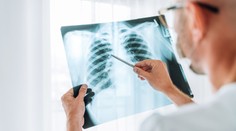

Zdravie Seniorke pomohla zachrániť život umelá inteligencia. Nástroj jej odhalil nádor na pľúcach Milan Špak 15. 12. 2024

Zdravie Nenápadné príznaky rakoviny pľúc: Ochorenie môžu prezradiť prsty na rukách Gabriela Šlebodová 27. 10. 2024